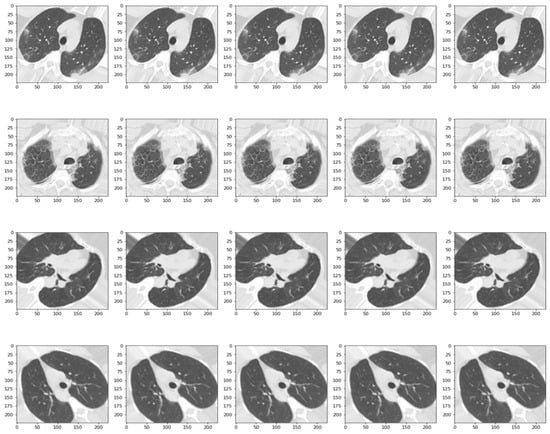

2.1. Data Collection and Pre-Processing

- CT-COV19 [22]—via IRB approval, CT-COV19 is a dataset of approximately 13,000 non-contrast lung CT scans in which chest cavity volume reconstructions are set at a slice thickness between 0.3 and 1 mm;

- COVID-19-CT [24]—all CT scans are classified into novel coronavirus pneumonia (NCP) due to the SARS-CoV-2 virus, common pneumonia, and normal controls being available globally to help clinicians and researchers fight the pandemic, where COVID-19 is making its presence felt;

- COVID-CT [25]—contains 349 CT samples belonging to 216 patients diagnosed positive for the COVID-19 virus and 397 CT images, with a negative diagnosis for COVID-19 having origins in bioRxiv and medRxiv servers;

- SARS-CoV-2 Ct-Scan-Dataset [26]—contains 1252 positive CT scans for SARS-CoV-2 (COVID-19) infection and 1230 CT scans for patients not infected with SARS-CoV-2, totaling 2482 samples collected from real patients in hospitals in Sao Paulo, Brazil.